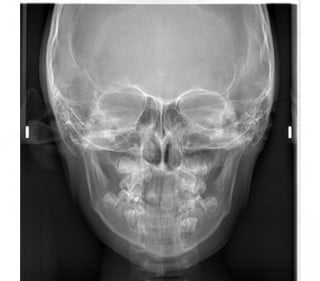

パノラマ(お口全体のレントゲン)・セファロ(お顔・手のレントゲン)・口腔内写真(現在の歯並びの写真)・顔写真・歯の型取り

をして丁寧に状態の確認を行います。

セファロ

顔貌の対称性/歯列幅/関節の形/咬合平面の傾斜 など